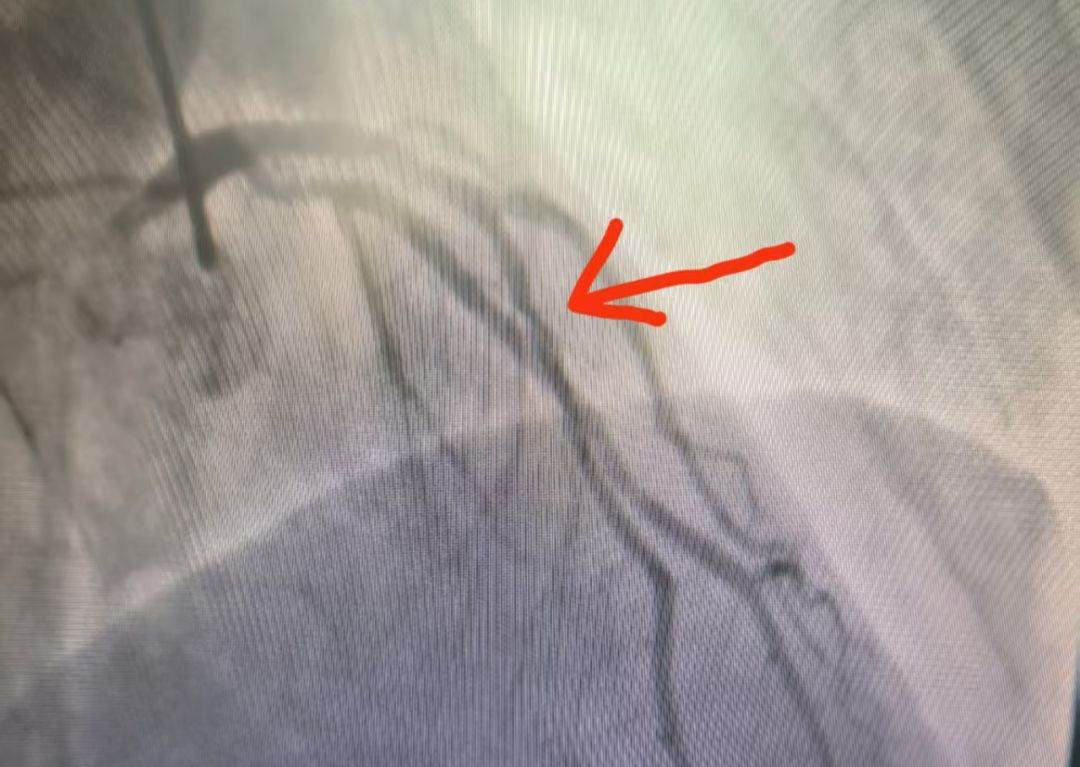

心血管疾病是威脅人類健康的“頭號殺手”,葫蘆島市第二人民醫(yī)院中醫(yī)科王崇權(quán)主任團隊在不斷努力下,找到了新的破解之道。王崇權(quán)主任團隊深諳“整體觀念、辨證論治”的中醫(yī)精髓,巧妙地將傳統(tǒng)中醫(yī)藥智慧與現(xiàn)代醫(yī)學技術(shù)相結(jié)合,在心血管危重癥干預(yù)領(lǐng)域取得了令人矚目的突破,為患者開辟了一條獨具特色的康復之路。 神奇療效,見證中醫(yī)力量 心血管疾病作為慢性疾病,病情遷延,復發(fā)率較高,聯(lián)合中醫(yī)藥的治療,可以取得顯著的效果。特別是在冠心病、心律失常、心衰、高血壓、失眠、焦慮、便秘、痛癥、體重管理等方面,尤為明顯。 病例一:頑固性早搏患者經(jīng)中藥調(diào)理1個月,24小時動態(tài)心電圖顯示早搏次數(shù)從34061次降至153次,睡眠質(zhì)量與精神狀態(tài)同步改善。 5月10日數(shù)據(jù) 7月1日數(shù)據(jù) 病例二:47歲心梗后心衰患者,在西醫(yī)規(guī)范治療基礎(chǔ)上配合中藥湯劑,心臟射血分數(shù)(EF值)從34%提升至50%,胸悶、氣短等癥狀明顯改善。 5月16日數(shù)據(jù) 7月1日數(shù)據(jù) 病例三:58歲男性反復胸痛,冠脈造影顯示前降支中段重度狹窄(70%),經(jīng)三個月中藥治療后復查冠脈CT,狹窄程度減輕為輕度(30%)。 治療前造影 治療后診斷結(jié)果 病例四:46歲男性,反復胸痛伴焦慮狀態(tài),湯藥治療后胸痛明顯緩解,復查冠脈較前明顯改善。 治療前 治療后 這四個典型病例充分展示了中醫(yī)藥在心血管疾病防治中的獨特優(yōu)勢。這種源于傳統(tǒng)醫(yī)學的整體調(diào)理理念,不僅針對病癥本身進行治療,更注重恢復機體的陰陽平衡,激發(fā)自身的修復能力,為心血管疾病患者提供了特色鮮明的治療選擇。 葫蘆島市第二人民醫(yī)院中醫(yī)科在王崇權(quán)主任的帶領(lǐng)下,持續(xù)深入挖掘中醫(yī)藥寶庫,致力于在心血管疾病防治領(lǐng)域開展更多的臨床實踐與研究,為提升人類健康水平貢獻中醫(yī)智慧。 中醫(yī)科簡介 葫蘆島市第二人民醫(yī)院中醫(yī)科集中醫(yī)預(yù)防、治療、康復、保健于一體,以深厚的中醫(yī)藥文化為底蘊,秉承“整體觀念,辨證論治”的核心思想,運用傳統(tǒng)中醫(yī)理論和方法,結(jié)合現(xiàn)代醫(yī)學技術(shù),為患者提供優(yōu)質(zhì)中醫(yī)診療服務(wù)。 運用中藥飲片、顆粒、膏方、針灸、推拿、拔罐、中藥外敷、刮痧、穴位貼敷、耳穴壓豆等多種方法辨證施治,針對不同病癥的病因病機,精準調(diào)節(jié)臟腑功能,實現(xiàn)內(nèi)外兼治,標本兼顧。 1、內(nèi)科疾病調(diào)治 高血壓、冠心?。ㄐ慕g痛)、心律失常、PCI術(shù)后康復、慢性疼痛、頑固性失眠、頭痛眩暈、疲勞綜合征及免疫力調(diào)節(jié)等。 2、亞健康狀態(tài)干預(yù) 基于中醫(yī)體質(zhì)辨識(氣虛/陽虛/陰虛/痰濕/濕熱等),針對性調(diào)理慢性疲勞、睡眠障礙、焦慮狀態(tài)及體質(zhì)偏頗。 3、腫瘤輔助療法 緩解放化療副作用(消化道反應(yīng)、骨髓抑制、癌因性疲乏),協(xié)同增強免疫功能,改善生存質(zhì)量。 4、精準體重管理 融合體質(zhì)辨證(BMI/體脂分析)、中藥內(nèi)調(diào)(代茶飲/膏方)、外治療法(針灸/穴位埋線/雷火灸)及個性化運動膳食指導,構(gòu)建科學減重體系。 人民醫(yī)院 人民名醫(yī) 王崇權(quán) 副主任中醫(yī)師 碩士研究生 ·葫蘆島第二人民醫(yī)院心臟中心門急診主任、中醫(yī)科主任 ·國家中醫(yī)藥管理局龍砂醫(yī)學流派五運六氣第四批傳承人 ·全國醫(yī)藥技術(shù)市場協(xié)會心衰防治專業(yè)委員會委員 ·中國醫(yī)藥信息學理事會心力衰竭學術(shù)委員會委員 ·中國民族醫(yī)藥學會委員 ·遼寧省中西醫(yī)介入委員會常務(wù)委員 ·葫蘆島醫(yī)學會心血管病分會委員 ·葫蘆島醫(yī)學會心電生理與起搏學會分會委員 ·葫蘆島市醫(yī)學會急診醫(yī)學分會委員 專業(yè)特色:師從遼寧中醫(yī)藥大學附屬醫(yī)院知名專家張明雪教授,從事臨床工作10余年,擅長胸痹、心悸、喘證、失眠等疾病的中醫(yī)傳統(tǒng)湯藥治療;中西醫(yī)結(jié)合治療冠心病、心力衰竭、高血壓、心律失常等心血管疾??;心血管疾病危重患者的搶救及急診PCI治療等。在涌泉貼、耳穴壓豆、穴位按摩、中藥足浴治療失眠等內(nèi)科疾病方面效果顯著。開設(shè)中醫(yī)減肥門診,中西醫(yī)結(jié)合進行系統(tǒng)體重管理。順利完成急性心肌梗死溶栓治療百余例,冠狀動脈造影及PCI手術(shù)2000余例,成功搶救危重患者數(shù)百例。 學術(shù)成就:多次前往北部戰(zhàn)區(qū)總醫(yī)院、遼寧中醫(yī)藥大學附屬醫(yī)院、大連市友誼醫(yī)院等知名醫(yī)院進修學習,在中西醫(yī)結(jié)合治療心血管疾病領(lǐng)域有所突破。參與編撰書籍《從溫病論治病毒性心肌炎》《 基于網(wǎng)絡(luò)藥理學探討肺癌培元固本法的用藥規(guī)律研究》《醫(yī)養(yǎng)結(jié)合概論》,發(fā)表《血府逐瘀湯聯(lián)合他汀治療高脂血癥療效分析》《歸脾湯加減結(jié)合降壓藥治療老年性高血壓臨床效果觀察》等多篇文章。參與課題《評價祛痰化瘀、益氣溫陽法治療冠心病合并緩慢性心律失常的臨床研究》《基于真實世界的冠心寧片治療穩(wěn)定性冠心病的多中心病例注冊登記研究》的臨床研究及病例收集分析。主持葫蘆島市課題《中醫(yī)聯(lián)合外治法通過調(diào)控RASS系統(tǒng)干預(yù)腎陽不足型高血壓研究》。 出診時間: ??健康體重管理門診:每周一上午(門診三樓4號診室) ??心內(nèi)中西醫(yī)科:每周二上午(心臟門急診4診室) 顧平 主治醫(yī)師 中醫(yī)內(nèi)科學碩士 ·葫蘆島市第二人民醫(yī)院中醫(yī)科主治醫(yī)師 ·遼寧省中醫(yī)藥學會針刀分會委員 ·江蘇省研究型醫(yī)院學會睡眠分會委員 ·江蘇省中醫(yī)藥學會針灸分會委員 專業(yè)特色:曾于中國中醫(yī)科學院西苑醫(yī)院進修心血管疾病相關(guān)的中醫(yī)治療。擅長中醫(yī)辨證方藥治療冠心病、心力衰竭、高血壓、焦慮證、抑郁證;針藥結(jié)合治療失眠癥、脾胃病;針灸治療頸肩腰腿痛;針灸美容及代謝綜合征的體重管理。先后發(fā)表5篇核心期刊論文。主持課題“加味二仙湯治療陰虛陽亢型高血壓病的血漿代謝組學研究”一項。參與編著《中醫(yī)藥治療病毒性心肌炎》和《冠心病證候研究》兩部著作。